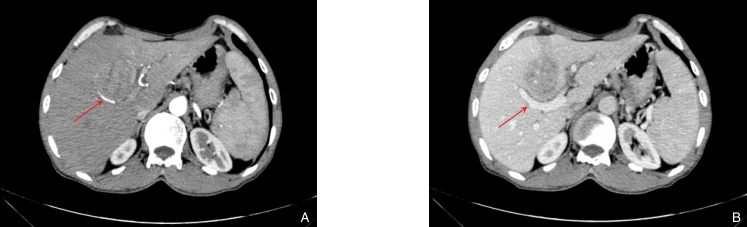

图1 术前腹部增强CT A:动脉期可见肝内肿块不均匀强化;B:门脉期见强化消退Fig.1